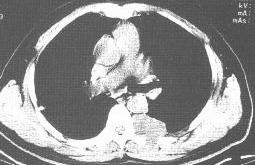

胸膜间皮瘤。CT平扫纵隔窗示左侧后胸壁、椎旁软组织密度肿块,并局部肋骨破坏。 | |

| 2.胸膜不规则增厚,呈大小不等的软组织肿物影,呈半球形或椭圆形,边界清楚,与胸壁成钝角,部分肿瘤有瘤蒂形成,随体位改变肿瘤位置和形态亦可改变。瘤周胸膜可呈结节状或凹凸不平的改变。弥漫型可侵犯纵隔、心包、胸壁以及对侧胸膜。形成纵隔固定、心包积液、胸壁软组织肿块、肺内大片或大块状浸润病变。 |

| 3.肋骨或椎体骨破坏。CT有时可见肿瘤内小点状钙化。CT增强扫描肿瘤病变明显强化。MRI上T2W呈高信号强度。 |